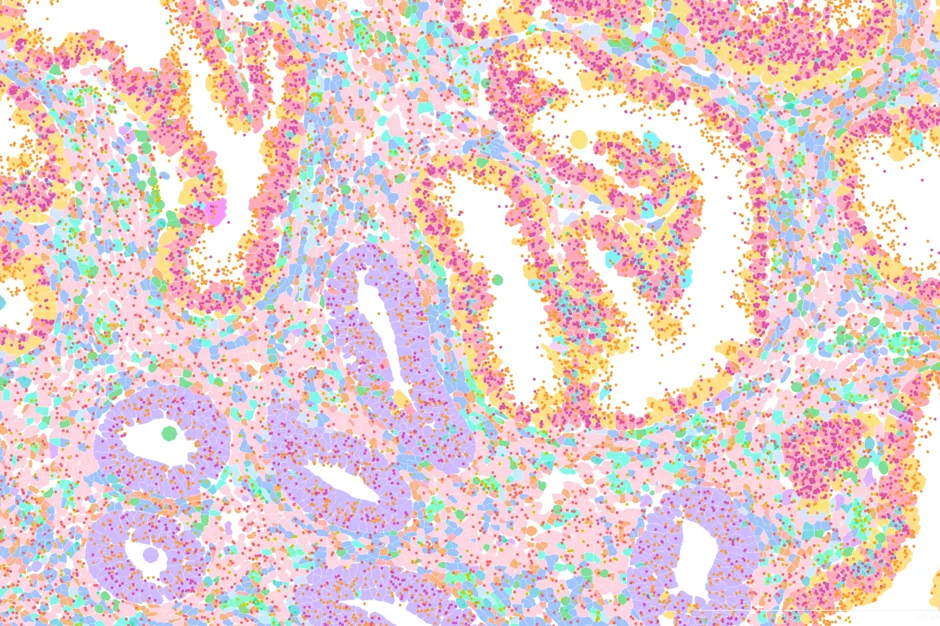

This colorful image maps the human endometrium at the single-cell level, with each color representing a different cell type or gene within the uterus’s lining. Yellow and dark pink represent the epithelial glandular cells— specialized epithelial cells that form glands to secrete various substances to prepare for and facilitate the embryo implantation and maintain pregnancy. Purple shows the basal epithelial cells, which contain progenitor cells located at the base of the endometrium. They are anchored to the basement membrane and serve as a source of new cells for the epithelium. The light pink, green and light and dark blues on the image show fibroblasts, which are cells that form and maintain connective tissue.

The dots on the image show different genes: orange (MUC1), pink (EPCAM), red (MME), and yellow (THY1).